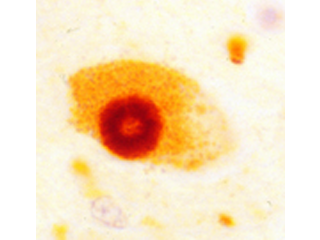

The Lewy body is the pathological hallmark of Parkinson's disease. Photo courtesy of Dr. Mel B. Feany.

Although two percent of the population over age 65 are clinically diagnosed with PD, the defining pathology of disease (alpha-synuclein Lewy bodies) is discovered in 20 percent of brains from population-based autopsy studies. We have participated in studies to better understand the clinical impact of this pathology, and its potential as an endophenotype for genetic analyses. In a study of 744 autopsies from older adults without a clinical diagnosis of PD, nearly a third showed evidence of post-mortem Lewy bodies and/or substantia nigra neurodegeneration, the defining pathologies of PD, and these changes were associated with parkinsonian motor signs proximate to death (Buchman et al. 2011). Therefore, PD-related pathology appears to be responsible for a much greater burden of age-related motor disability than currently realized. Discovery of the underlying genetic factors may allow us to identify susceptible individuals and ultimately intervene with effective therapies.